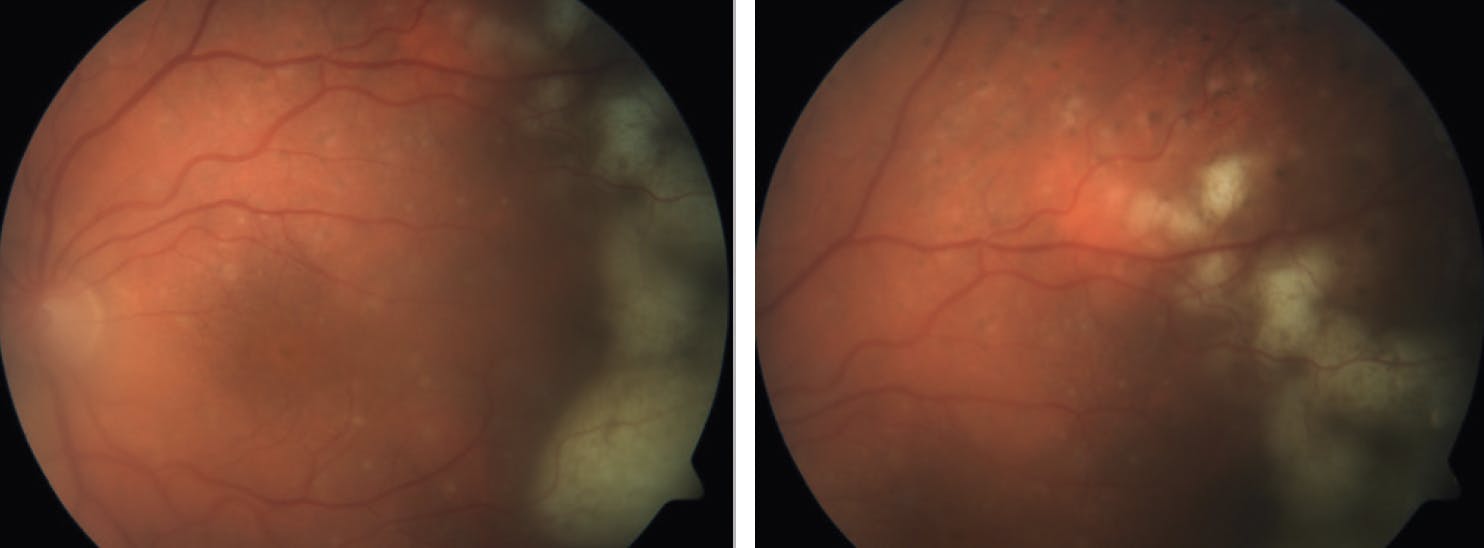

• Ocular Imaging: Multimodal imaging, including fundus autofluorescence (Figure 2), OCT (Figure 3), fluorescein angiography, and contrast-enhanced MRI of the brain, is also important to investigate.

<p>Figure 2. Fundus autofluorescence of the right (A) and left (B) eye of a 66-year-old woman showed a granular hyper- and hypoautofluorescence pattern indicative of VRL. This patient had a vitrectomy specimen labeled as “highly suspicious” for lymphoma and, indeed, developed brain lymphoma 2 months after presenting with ocular symptoms.</p>

Figure 2. Fundus autofluorescence of the right (A) and left (B) eye of a 66-year-old woman showed a granular hyper- and hypoautofluorescence pattern indicative of VRL. This patient had a vitrectomy specimen labeled as “highly suspicious” for lymphoma and, indeed, developed brain lymphoma 2 months after presenting with ocular symptoms.